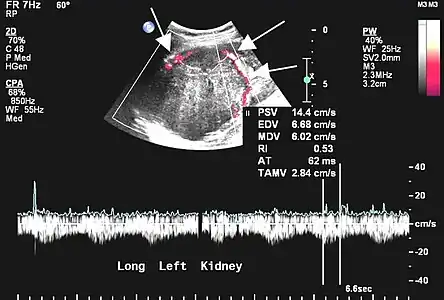

L'échographie est rarement réalisée pour les localisations pleurales, mais peut être utile dans les autres localisations[45]. Les tumeurs fibreuses solitaires se présentent comme des masses homogènes, hypoéchogènes et bien délimitées ; le doppler permet de visualiser la vascularisation. Les tumeurs pleurales se mobilisent avec les mouvements ventilatoires[45].